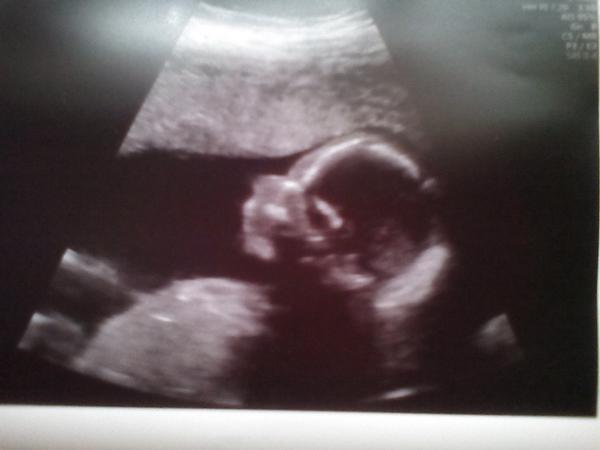

Ahoj holky, tak my jsme byli dneska na prvním UTZ po transferu. Viděli jsme nádherný tlukot srdíčka a odpovídáme 6+6tt ❤ Bylo to hrozně dojemné a doufám, že nejdřív za pár let se tam zase ukážeme 😎 Za nás tedy péče a profesionalita (a samozřejmě taky ceny 😀😀) v pronatalu na jedničku a doufám, že všem se brzy taky zadaří!!!!!!!!! 🤰